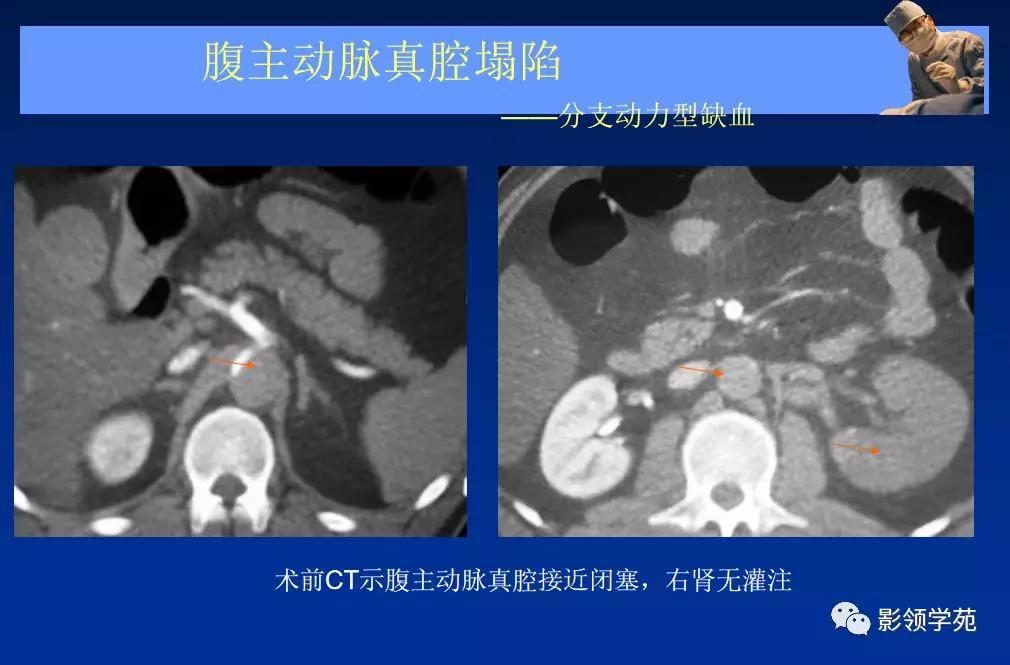

- 主动脉夹层(aortic dissection, AD)